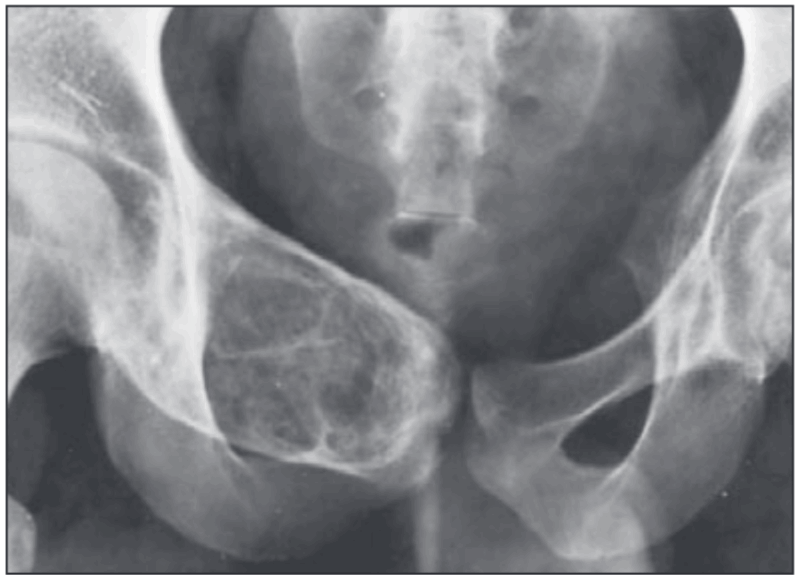

持参されたX線写真を見たところ, 恥骨が溶けて壊れているのと, その内部に骨が白くなって硬くなっている, あるいはカルシウム成分が濃くなっている(石灰化している)所見が認められました. 骨の悪性腫瘍が疑われる所見でした. 今日中に一通りの検査を行うことにして, 血液検査, CT, MRIをオーダーしました.

右の恥骨がふくらんで大きくなっています.

引用元:Eisenberg RL. Bubbly Lesions of Bone. AJR Am J Roentgenol. 2009. 193.

CTを見ると, 恥骨の一部がふくらむように大きくなっていました. 硬い骨がふくらむことは短期間には起こりえないので, かなり以前(数年以上前)から骨の中に非常にゆっくりと大きくなる良性骨腫瘍が存在していて, それが骨をふくらませていたところに, 一部が悪性腫瘍に変化した(がん化)したため, 骨が溶けて壊れている状態を疑いました. CTの所見からは, 線維性骨異形成という腫瘍類似疾患と判断しました.